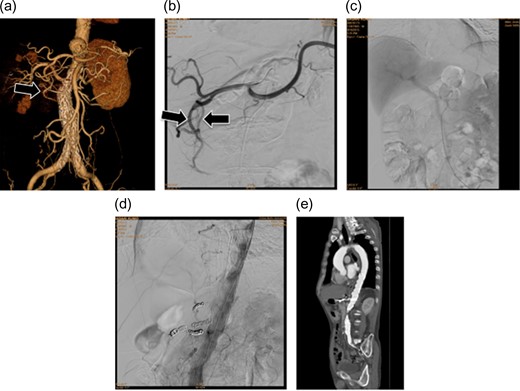

(a and b) Preoperative contrast-eCT. (c and d) eCT performed on postoperative day 13. A cyst is seen on the pancreatic tail (black arrow), while no contrast effect is seen in the spleen (white arrow). (e and f) CT performed on postoperative day 21. The pancreatic cyst has started to shrink. Part of the spleen becoming necrotic does not conflict with an etiology of ischemia due to embolization of the splenic artery.

The patient did not have preoperative risk factors for pancreatitis. Additionally, CT images taken at the arterial and late phases (180 s) did not show a contrast effect in the splenic artery distal to the embolism or the spleen. Pancreatitis occurred immediately after the arteries perfusing the pancreas were surgically embolized. Therefore, we diagnosed pancreatitis due to reduced pancreatic blood flow secondary to embolization (Fig. 2).